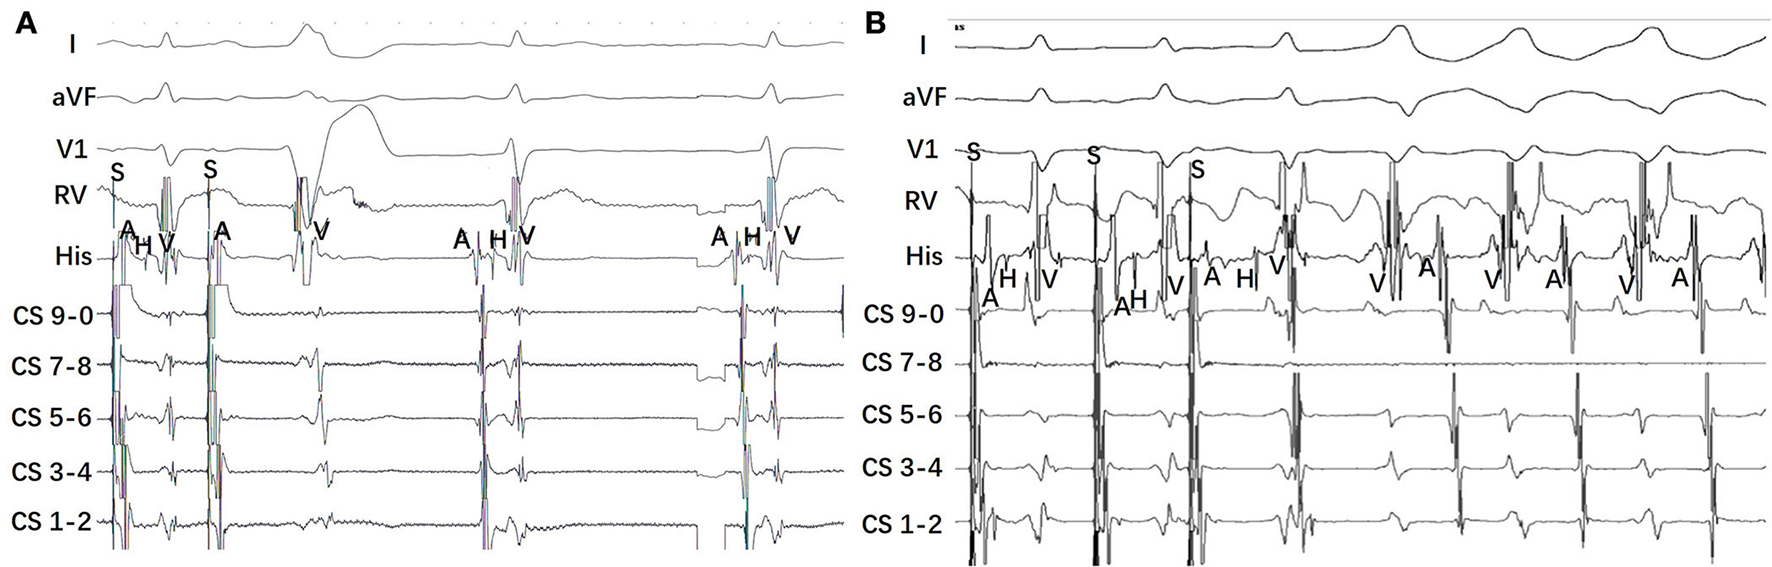

Figure 2

Representative intracardiac electrocardiogram from a patient with right-sided MAP and a patient with left-sided MAP. (A) Atrial programmed atrial stimulation (S1S1) induced a pre-excitation of QRS complex with LBBB pattern. It presents antegrade long conduction with lengthening of the A-H interval and A-V interval, a contemporary shortening of the H-V interval. (B) Atrial programmed stimulation (S1S1) induced tachycardiac with a broad QRS complex. The tachycardia has an RBBB pattern, long AV interval, and short VA interval. The earliest atrial activation was detected at the His-bundle electrodes during the tachycardia.

Tables 2, 3 show the EPS characteristics of the patients studied. Atrial pacing protocol showed manifest pre-excitation with decremental AV conduction in all patients. With incremental atrial pacing, AH was prolonged, HV was shortened, and tachycardia was induced (Figure 2).